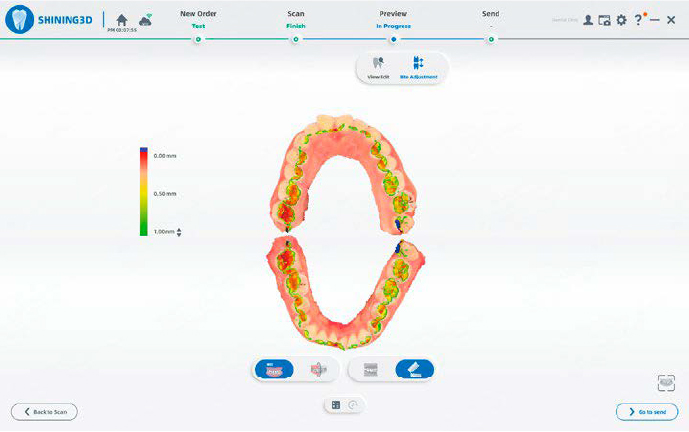

RILEVAMENTO DEI CONTATTI OCCLUSALI

Visualizzazione intuitiva dei contatti tramite mappa cromatica e vista sezionale, per valutare in modo efficiente le relazioni occlusali.